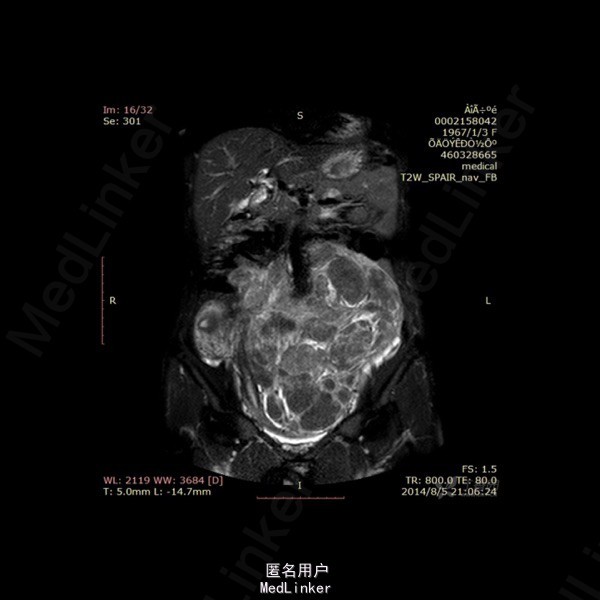

影像表现:左侧附件区示一巨大的病变,呈长T1长T2异常信号影,期内多发分隔,增强后呈不均匀强化,强化较明显。DWI示低信号。总的来看,病变为一个巨大肿块,内有分隔,境界较清。 诊断:我认为首选左侧阔韧带子宫肌瘤可能性大。由于其短期内增大,不除外瘤内出血的可能。 转于:丁香园